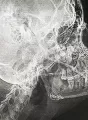

Первые дни только привыкал к шинам, но быстро адаптировался, так как не впервой. От госпитализации я отказался, решил, что в домашних условиях справлюсь. Сделал контрольный снимок, проконсультировался с хирургом-стоматологом и он, посмотрев на снимок и на шины, сказал, что процесс заживления идёт нормально.

Снимок прилагаю (был сделан на 5-й день после шинирования).